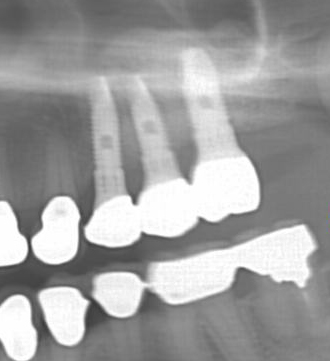

CT検査をしてみると,確かにインプラントを埋入したい部位に骨が全然無い(CT上で黒く映っている)のが分かります。

治療後のレントゲン写真です。長さ,太さの十分なインプラントが再生した骨によって支えられているのが分かります。